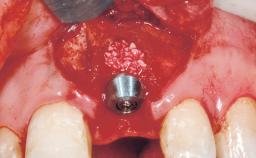

Immediate Flapless Placement of an Implant in a Maxillary Left Central Incisor Site

A 42-year-old female patient was referred to our clinic at the School of Dentistry of the University of São Paulo in November 2004, presenting a deficient restoration in the upper left central incisor. The clinical examination revealed no gingival retraction or any signs of gingival inflammation and, therefore, previous periodontal treatment was not considered. The patient presented a high lip line at full smile and a thin tissue biotype. This combination characterized a high-risk situation from an anatomic point of view, which required careful preoperative planning and cautious surgical execution.

Placement Protocol Immediate implant placement

Socket Integrity Sufficient, with intact bone walls

Bone Volume Sufficient, with intact walls